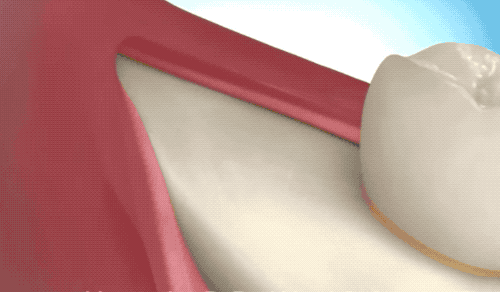

接著介紹下小編的牙齒類型,堪稱 hard 模式的橫阻生智齒。一般生長(zhǎng)情況也分兩種,一種是已經(jīng)出肉的,一種是還未出肉的,操作都差不多,我們就直接看下圖的介紹了。

露出牙槽骨后,先削除一部分骨頭,露出躺臥如睡美人的橫阻生智齒...如果是已經(jīng)出肉的智齒,就沒這一步了。

請(qǐng)出那令人聞聲喪膽的牙科渦輪機(jī),先分割智齒,撬出塊頭過(guò)大的牙冠來(lái)...再把牙根磨切兩半,依次撬出來(lái)。當(dāng)然這樣的操作并不都是必須的,牙醫(yī)會(huì)依據(jù)當(dāng)時(shí)的可操作性去處理,畢竟每個(gè)哈姆雷特的橫阻生智齒也都可能長(zhǎng)得不一樣。